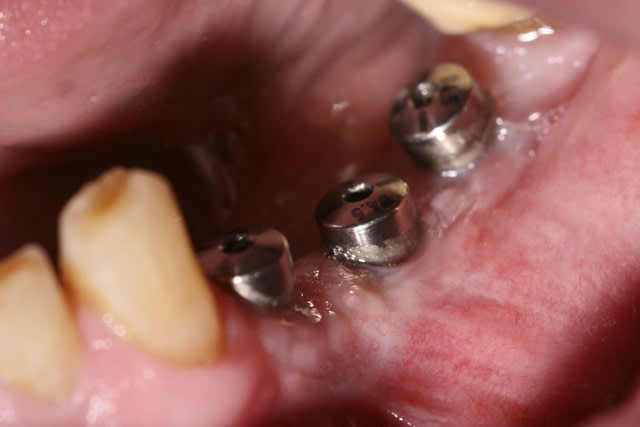

image 12 et 13: réouverture, forage et pose des implants ( les implants ont été posés par le DR A. L dans le 31)

J'ai des photos de la réouverture de ce cas et de la pose des implants, j'ai même fait une expansion, pour justifier de la solidité de l’attache des blocs...

image1 réouverture et dépose du matériel ( du tissu fibreux s'est insinué dans les fentes mésiales et distales que j'ai du cureter)

image2 pose d'une membrane pour faire une ROG sur ces dites fentes

image 3 réentrée à 3 mois

image4 pose des implants + re ROG autogène)

image 5 vis de cicat ( re 2mois )

image6 visualisation de la cicat gingivale 6 semaines après la pose des vis de cicat.